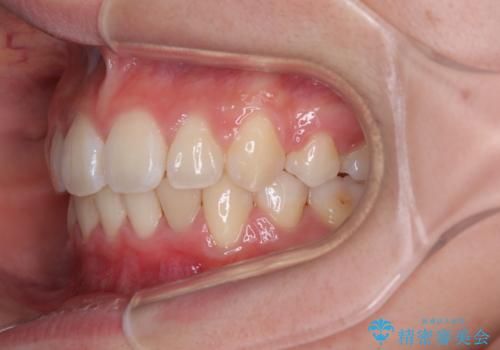

飛び出した上顎前歯 ワイヤー装置にて抜歯矯正治療

- 前に傾斜して飛び出した上顎前歯を気にして来院された患者様です。

上下前歯の前後差が大きく、下顎前歯が隠れるほど深い咬合で、咬合力が強い状態でした。

口元の突出感を改善するために、上下左右の第一小臼歯4本を抜歯し、ワイヤー装置にて矯正治療を行うこととしました。

深い咬み合わせの改善に時間がかかりましたが、下顎前歯がしっかりと見えるまでに整えることができ、口元の突出感も大幅に改善することができました。